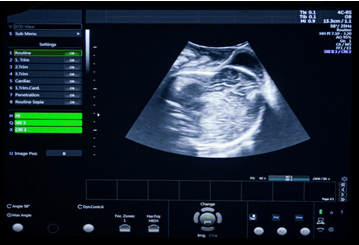

Doppler sensitivity and measurement accuracy measurements, as well as image quality assessment follow the FDA diagnostic ultrasound guidance Clinical safety and effectiveness requirements as well as the JIS T 1501 test standard for imaging performance of diagnostic ultrasound systems.

Reports include Doppler sensitivity of diagnostic ultrasound transducers and systems, including maximum penetration depth, using string and flow phantoms for simulated use, in Color, PW and CW modes. Measurement accuracy includes the accuracy of the distance measurements, lateral and axial resolution, maximum penetration, as well as velocity measurement accuracy in CW and PW modes, among others.